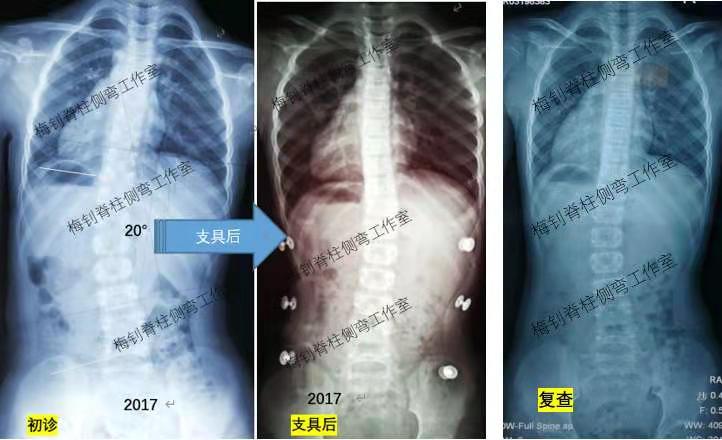

女孩,2017年发现侧弯,当年9岁,侧弯20度,穿戴支具后处于过矫状态。尽管支具效果不错,患儿身高也不断增长,但每隔半年拍片复查都会有大幅度反弹。好在患者家长听从我们的建议,坚持佩戴支具,今年2月,患儿脱支具30小时拍片,脊柱终于有所稳定,如下图: